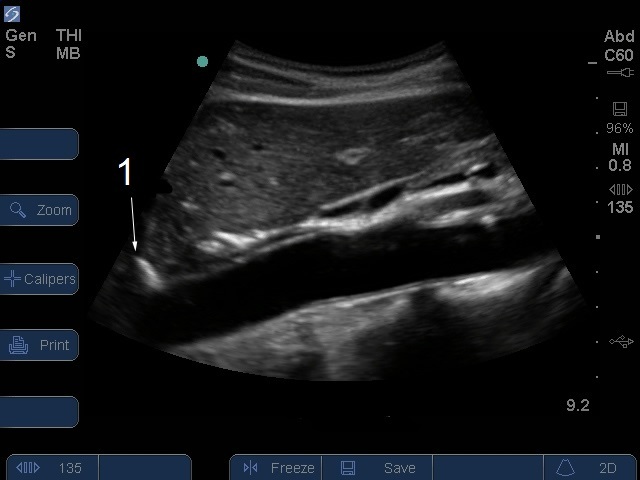

Bild: S-Serie, proximale Aorta, sagittale Ansicht/Zwerchfell

Zwerchfell